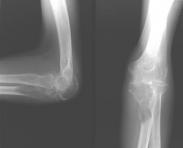

骨腫瘤是發生于骨骼或其附屬組織(血管、神經、骨髓等)的腫瘤,是常見病。同身體其它組織一樣,其確切病因不明;骨腫瘤有良性,惡性之分,良性骨腫瘤易根治,預后良好,惡性骨腫瘤發展迅速,預后不佳,死亡率高,至今尚無滿意的治療方法。惡性骨腫瘤可以是原發的,也可以是繼發的,從體內其它組織或器官的惡性腫瘤經血液循環,淋巴系統轉移至骨骼或直接侵犯骨骼。還有一類病損稱瘤樣病變,腫瘤樣病變的組織不具有腫瘤細胞形態的特點,但其生態和行為都具有腫瘤的破壞性,一般較局限,易根治。